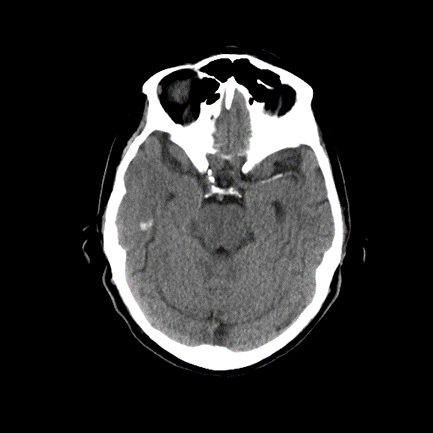

15/ The patient is kept in the ICU and ultimately undergoes #angiogram. Notice the area of perfusional deficit along the posterior MCA division: